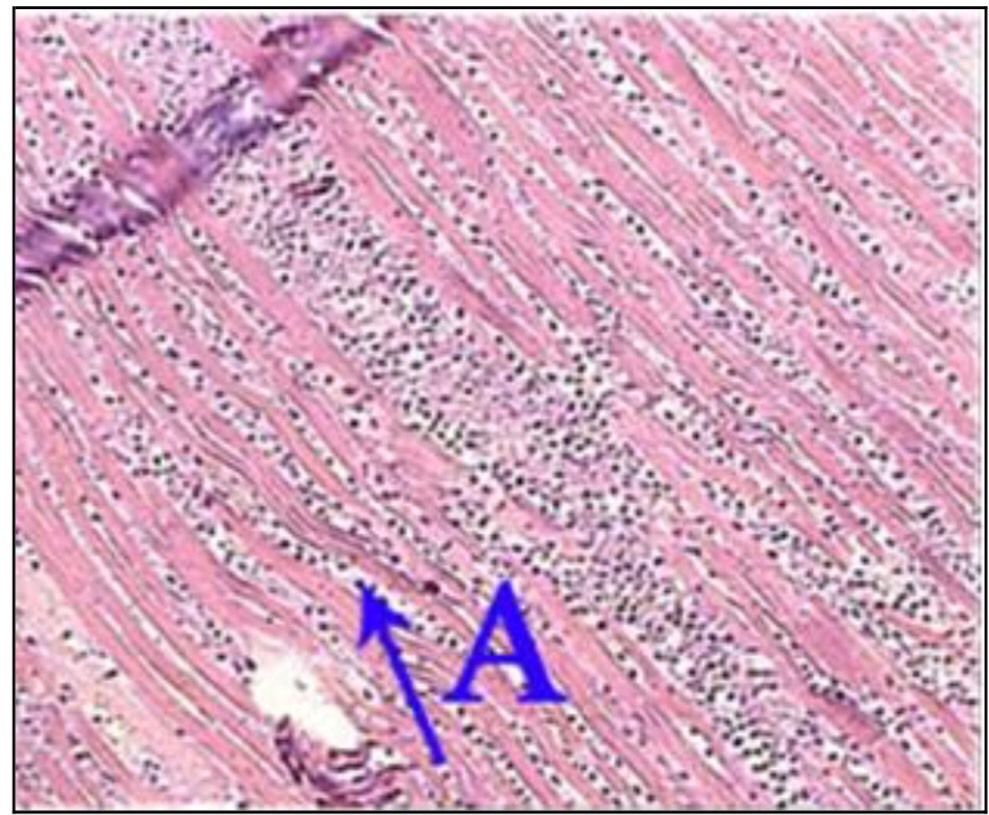

Question 82

Question

What is the correct answer at point A?

Answer

• - endomysium infiltré d’œdème

• - cellules myocardiques nécrosées

• - striation transversale

• - cellule myocardique dégénérée

• - cellule myocardique survivante

Question 83

What is the correct answer at point B?

Question 84

What is the correct answer at point C?

Question 85

What is the correct answer at point D?

Question 86

What is the correct answer at point E?